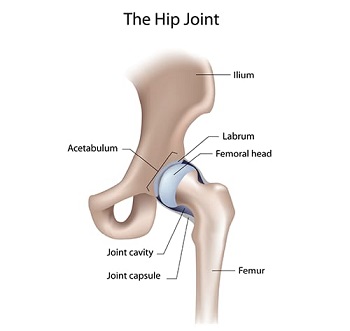

Hip Joint Preservation

The hip joint stands as one of the most vital joints in the human body. It bears the weight of the body and is essential for maintaining balance. This pivotal joint connects the thigh bone to the pelvis, boasting a ball-and-socket design that combines remarkable strength and flexibility. This construction allows for the extensive range of motion necessary for everyday activities, underscoring the hip's importance in our daily lives.